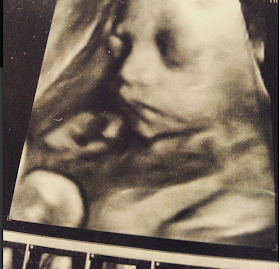

| foto ini diambil pake usg 3D, pertama kalinya dia mau ngeliatin muka. jaiiimmm banget anaknya hihihi |